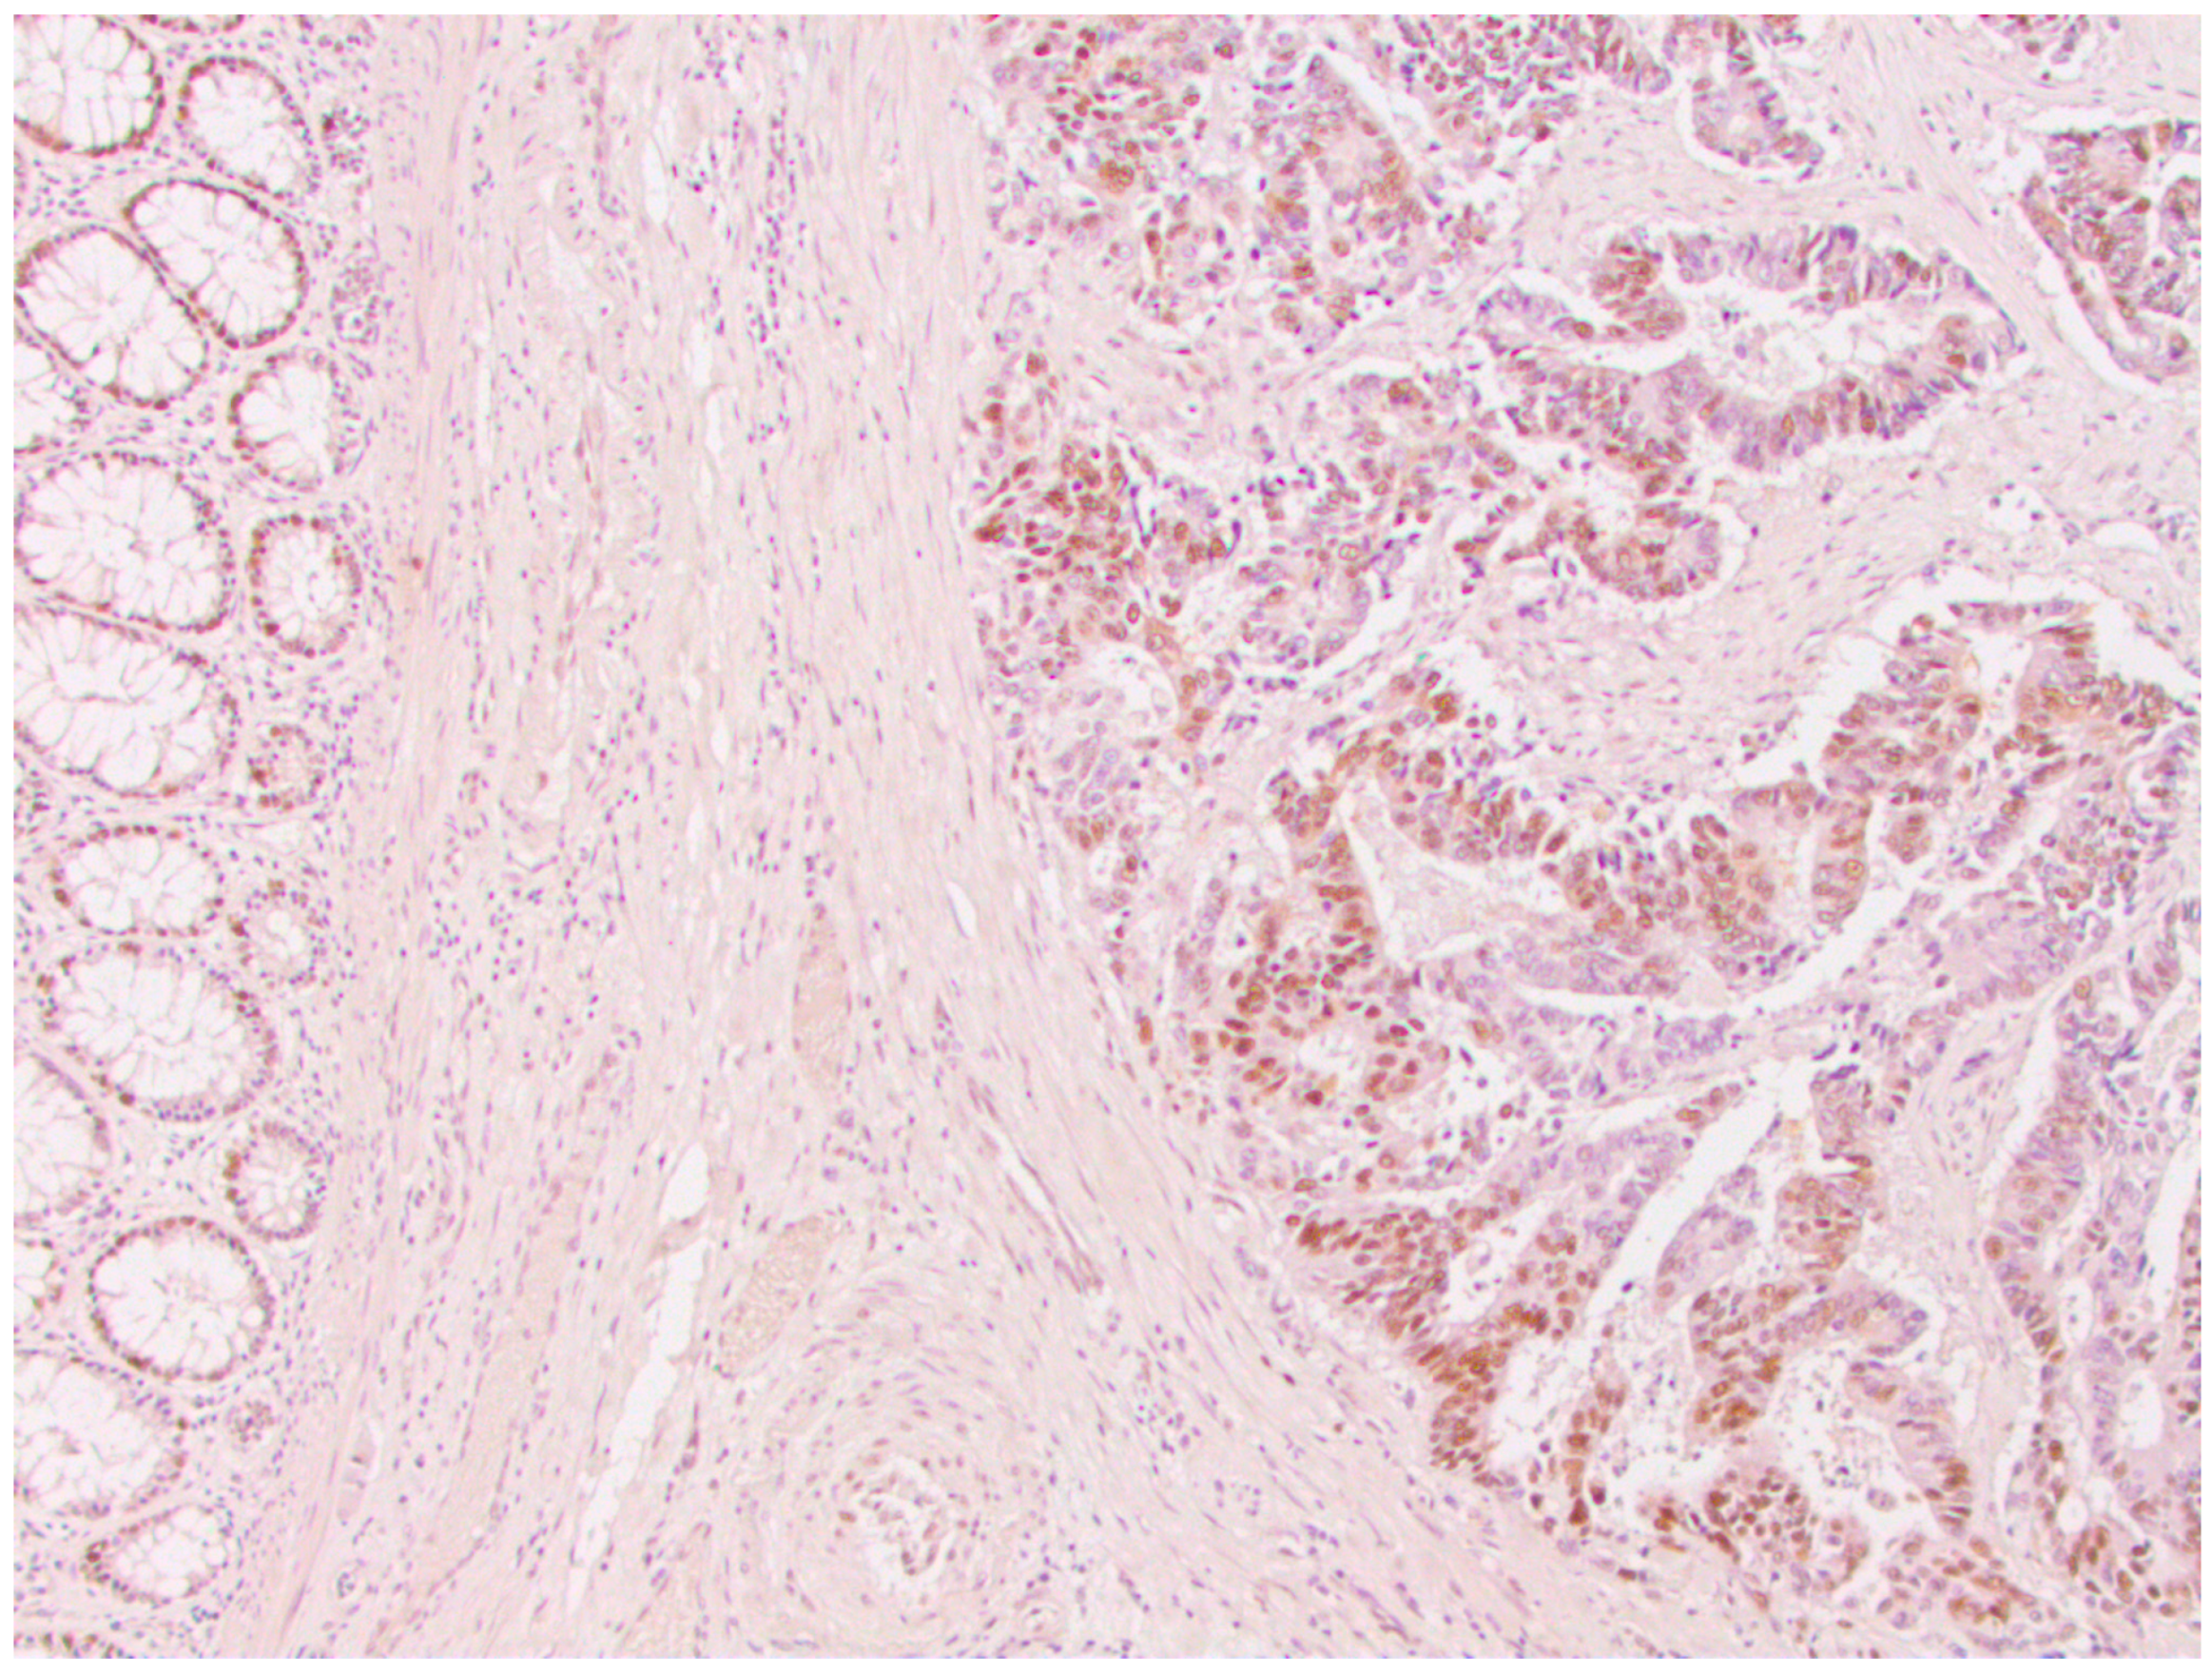

From a total of 104 patients with colorectal cancer, immunohistochemical analysis of the expression of all four MMR proteins showed that heterogeneous expression of MMR proteins (as well as deficient immunoreactivity of tumor cells (Figure 1) was present in 12 cases, while proficient expression of MMR proteins was detected in 80 tumors (Figure 2). Heterogeneous expression of PMS2 protein and heterodimeric pair MLH1/PMS2 was found in two tumors, MSH2/MSH6 was found in seven tumors (two of which also showed heterogeneity for MLH1/PMS2) and MSH6 was found only in one tumor. In seven out of twelve tumors micromorphologically, both forms of heterogeneous protein expression coexisted in the tumor tissue as intraglandular and zonal heterogeneity (Figure 3). Isolated intraglandular heterogeneous protein expression was found in two tumors (Figure 4), while zonal heterogeneity was present in three tumors (Figure 5).

Figure 1. Deficient nuclear expression of MLH1 protein in colorectal cancer, ×100.

Figure 3. Zonal and intraglandular distribution of heterogeneous nuclear expression of MLH1 protein in colorectal cancer, ×100.